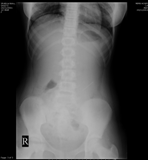

A 13 year old girl with a DOUBT that she had swallowed a single end pointed needle 30 minutes prior to attending the fast track op.

With these X RAY ,

doubt is cleared , there is no forign body

BUT…..

Most object traverse git without difficulty, but some sharp objects may need endoscopic removal